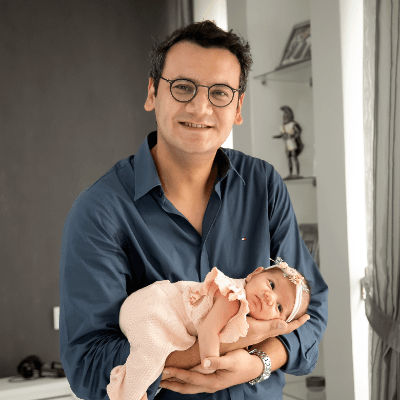

The mother was sent to The Institute for Mother and Child Care in Prague - Podolí, Czech Republic, for consultation and further management. A eutrophic male newborn was delivered via cesarean section at 38 weeks and 3 days due to non-progressive labor.

Diagnosis of hemangioma-hemangioendothelioma was clinically confirmed after delivery. The baby was placed on Propranolol treatment. At the time of posting this case, the baby is four months old and is doing well. The size of the tumorous mass diminishes gradually, and so no surgical treatment has been recommended thus far.